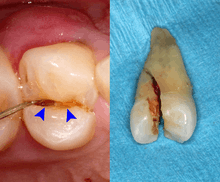

Dental trauma and cracked tooth syndrome

Cracked tooth syndrome refers to a highly variable[29] set of pain-sensitivity symptoms that may accompany a tooth fracture, usually sporadic, sharp pain that occurs during biting or with release of biting pressure,[30] or relieved by releasing pressure on the tooth.[9]:24 The term is falling into disfavor and has given way to the more generalized description of fractures and cracks of the tooth, which allows for the wide variations in signs, symptoms, and prognosis for traumatized teeth. A fracture of a tooth can involve the enamel, dentin, and/or pulp, and can be orientated horizontally or vertically.[9]:24–25 Fractured or cracked teeth can cause pain via several mechanisms, including dentin hypersensitivity, pulpitis (reversible or irreversible), or periodontal pain. Accordingly, there is no single test or combination of symptoms that accurately diagnose a fracture or crack, although when pain can be stimulated by causing separation of the cusps of the tooth, it's highly suggestive of the disorder.[9]:27–31 Vertical fractures can be very difficult to identify because the crack can rarely be probed[9]:27 or seen on radiographs, as the fracture runs in the plane of conventional films (similar to how the split between two adjacent panes of glass is invisible when facing them).[9]:28–9

When toothache results from dental trauma (regardless of the exact pulpal or periodontal diagnosis), the treatment and prognosis is dependent on the extent of damage to the tooth, the stage of development of the tooth, the degree of displacement or, when the tooth is avulsed, the time out of the socket and the starting health of the tooth and bone. Because of the high variation in treatment and prognosis, dentists often use trauma guides to help determine prognosis and direct treatment decisions.[31][32]

The prognosis for a cracked tooth varies with the extent of the fracture. Those cracks that are irritating the pulp but do not extend through the pulp chamber can be amenable to stabilizing dental restorations such as a crown or composite resin. Should the fracture extend though the pulp chamber and into the root, the prognosis of the tooth is hopeless.[9]:25